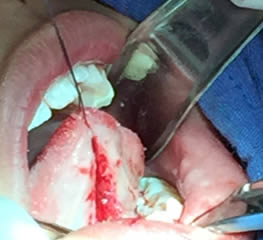

• Se realizó una incisión horizontal en la parte media del frenillo con hoja de bisturí No. 15 y mango No. 3, posteriormente se comenzó a cortar el frenillo de arriba abajo cuidando la anatomía de la región y la zona de las carúnculas sublinguales de los conductos de Wharton y Rivini. (Figuras 5 y 6).

Figuras 5 y 6. Incisión y corte del frenillo.

• Se eliminó el frenillo en su totalidad  con la ayuda de tijeras iris recta y hoja de bisturí del No. 15 así como todo el tejido residual fibroso correspondiente al frenillo. Se realizó genioplastia con pinza de mosco y disección roma para liberar adecuadamente la inserción frénica hasta la cara lingual de los incisivos inferiores. (Figuras  7, 8 y 9)

Figuras 7 y 8. Eliminación total del frenillo y genioplastia